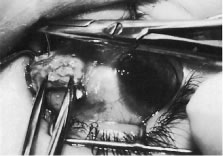

The surgeon cuts the intermuscular septa free from the muscle capsule (Fig. 67). A Castroviejo caliper is used to measure the amount of tendon that will be resected (Fig. 68). A Jameson resection clamp is placed on the muscle at the point of anticipated resection. Measurement is made from the portion of tendon that is on the posterior edge of the Jameson hook to the resection clamp. Exposure is facilitated with a Desmarres retractor.

|

|

The muscle is cut free from its insertion (Fig. 69). The surgeon holds the Jameson clamp to elevate the muscle from the globe, and, using the other hand, the surgeon cuts the muscle free from the globe. The muscle stump is cut so that it is flush with the globe.

|